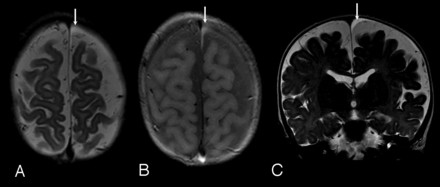

The SDC were identified initially on CT in 2 cases and on MRI in 4 (On-line Table). All SDC cases were referred because of macrocrania. Both CT cases had MRI within 9 days, which confirmed the CT findings. SDC were bilateral in 2 cases and unilateral in 4, localized over the convexities, with a mean size of 5.4 mm (range, 1–9.6 mm). In 4 cases (cases 2, 3, 5, and 6), the SDC were homogeneous, unilateral, and small in size, with similar features on MRI (Fig 1). None of these subjects had recent (within 2 weeks) CT imaging for review. In 2 cases, the SDC were larger, bilateral, and complex in appearance. In case 4, there were heterogeneous signal changes on MRI and increased attenuation on CT, which suggests recent hemorrhage with identified membranes within the collections (Fig 2). In case 1, there was heterogeneous internal signal with visible membranes and different signal intensity components. No CT or gradient-echo evidence of acute hemorrhage was identified.

Case 3. A, Axial FSE T2-weighted image. B, Axial proton density–weighted image. C, Coronal FSE T2-weighted image; 8-month-old girl. Clinical indicatin for examination: macrocrania. Typical small homogeneous subdural collection, similar to those identified in cases 2, 5, and 6. Note diffuse prominence of subarachnoid spaces. Small left frontal vertex subdural collection is identified (arrows), slightly hyperintense to CSF on T2-weighted images (A and C), and moderately hyperintense to CSF on proton density images (B). The collection was isointense to CSF on T1-weighted images and showed no blooming on gradient-echo sequences. Follow-up CT 3 months later showed decrease in prominence of the subarachnoid space, normal ventricles, and no evidence of subdural collection.